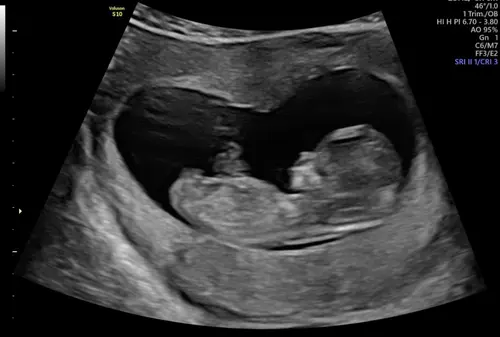

Zo intens spannend, van de eerste echo met 7+2 moeten wachten tot vandaag 11+2. Maar het was het wachten waard en we hebben een super goede 2e echo gehad! ❤️ datum stond al vast ivm icsi 01-08-2026, groei loopt wel 2 dagen voor 🤗🥰

Vandaag een goede termijnecho gehad. Weer 2 dagen naar voren gezet dus nu 11w+2d. Uitgerekende datum staat vast op 2 augustus. 🩵🩷

Termijn echo van 10 +4 ons kindje was 2 weken geleden 8+4 dus echt mooier kan niet! Mooie walnoot hersentjes gezien , er werd nog naar ons gezwaaid door ons kindje en ook het blaasje was al te zien. De verloskundige was onwijs tevreden! En wij ? Wij ZO trots

Hier 9 weken en 1 dag 🥰 mooi kloppend hartje en armen en benen druk aan het bewegen